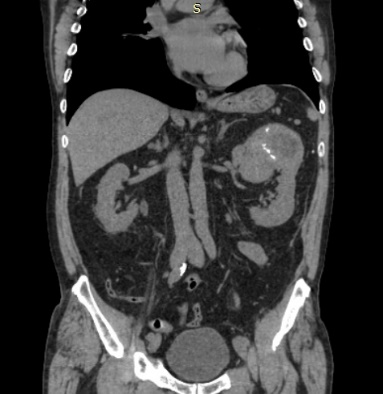

Se solicita urotomografía con contraste endovenoso evidenciando tumor renal izquierdo de aspecto sólido, heterogéneo, hipodenso, redondeado, de bordes circunscritos con realce heterogéneo posterior a la administración de contraste endovenoso y calcificaciones multifocales gruesas en su espesor que mide 10,4 cm x 9,1 cm x 10,3 cm, ubicada en polo superior que condiciona cambios en la arquitectura renal, se observan adecuados planos de clivaje con estructuras adyacentes, no hay dilatación del sistema colector, adecuada repleción de estructuras vasculares posteriores a la administración de contraste endovenoso son defectos de llenado, así como del sistema colector en fase de eliminación. No se reconocen adenopatías loco regionales. Se observan cambios en la grasa perirrenal posterior ipsilateral que pudiera estar en relación con antecedente.